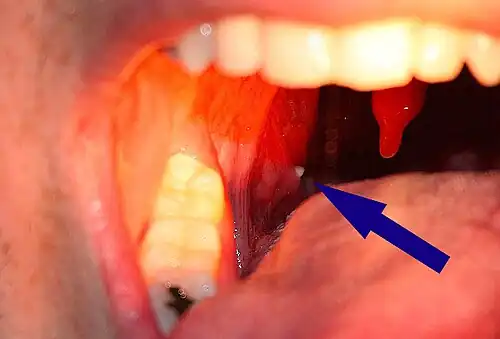

Tonsil stones, also known as tonsilloliths, are mineralizations of debris within the crevices of the tonsils.[1][3] When not mineralized, the presence of debris is known as chronic caseous tonsillitis (CCT).[1] Symptoms may include bad breath,[1] foreign body sensation, sore throat, pain or discomfort with swallowing, and cough.[4] Generally there is no pain, though there may be the feeling of something present.[1] The presence of tonsil stones may be otherwise undetectable; however, some people have reported seeing white material in the rear of their throat.

A tonsillolith protrudes from the tonsil -

Large tonsillolith half exposed on tonsil

Closeup of a tonsillolith

Enlarged tonsil stones

Much rarer than the typical tonsil stones are giant tonsilloliths. Giant tonsilloliths may often be mistaken for other oral maladies, including peritonsillar abscess, and tumors of the tonsil.[17] On average, tonsil stones should appear within a similar range of the image shown here; however, individuals with extenuating cases have been reported. In these instances, extensive care such as extraction by a licensed medical professional may be needed.